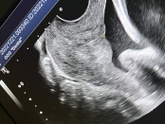

Девочки???вот посмотрите пожалуйста, вчера ходила на цервикометрию,даже сфотографировала, это же нормально все с ней?Я просто не понимаю почему все мерят по разному?даже 23 мерили как-то,ну не врач узист, а гинеколог просто? может я что-то не понимаю … Читать далее